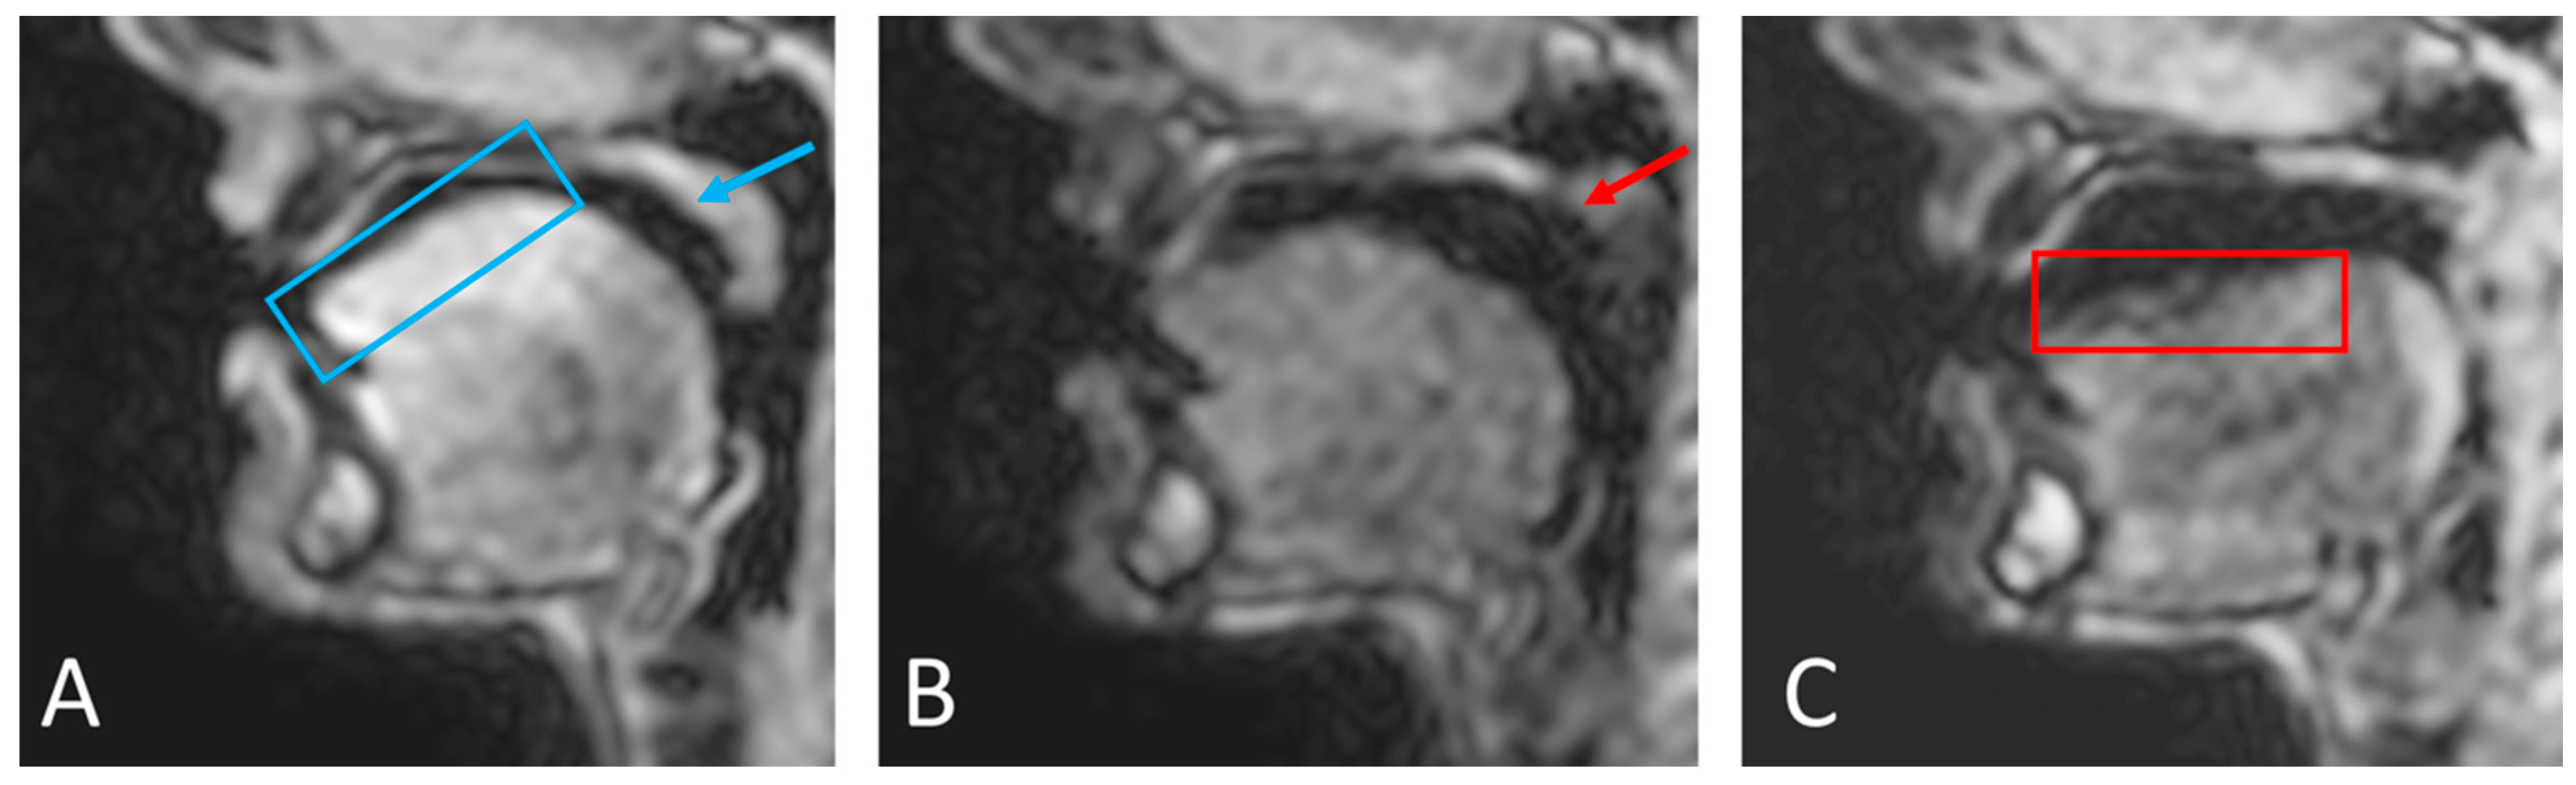

First, an automatic segmentation was run based on edge detection and contrast between tissues. Although this gives a relatively good result, manual adjustments were required especially in regions where signal drop-out due to off-resonance and susceptibility are known to occur. In the upper vocal tract, this is particularly the case when the velum is in a high position and at the back of the tongue in certain phonics [4,8]. Example images are shown in Figure 6 to illustrate this problem in the velum and the tongue. However, all regions that were not fully anatomically correct were successfully corrected with the extra steps described in the methodology (Figure 3). It is worth noting that the subject used for this study did not have any dental work or orthodontics; those can impact the image quality [88] and would lead to increased problem when segmenting the images; hence, more corrections would be needed to create anatomically correct regions in the phantom.

Figure 6.

Varying image quality through the frames will have an effect on the initial automatic segmentation. While the velum (blue arrow) and tongue surface (blue box) can be easily automatically segmented in image (A), the automatic segmentation of the velum (red arrow) in image (B) and the tongue (red box) in image (C) will need manual corrections because of the signal drop-outs and artefacts caused by off-resonance.